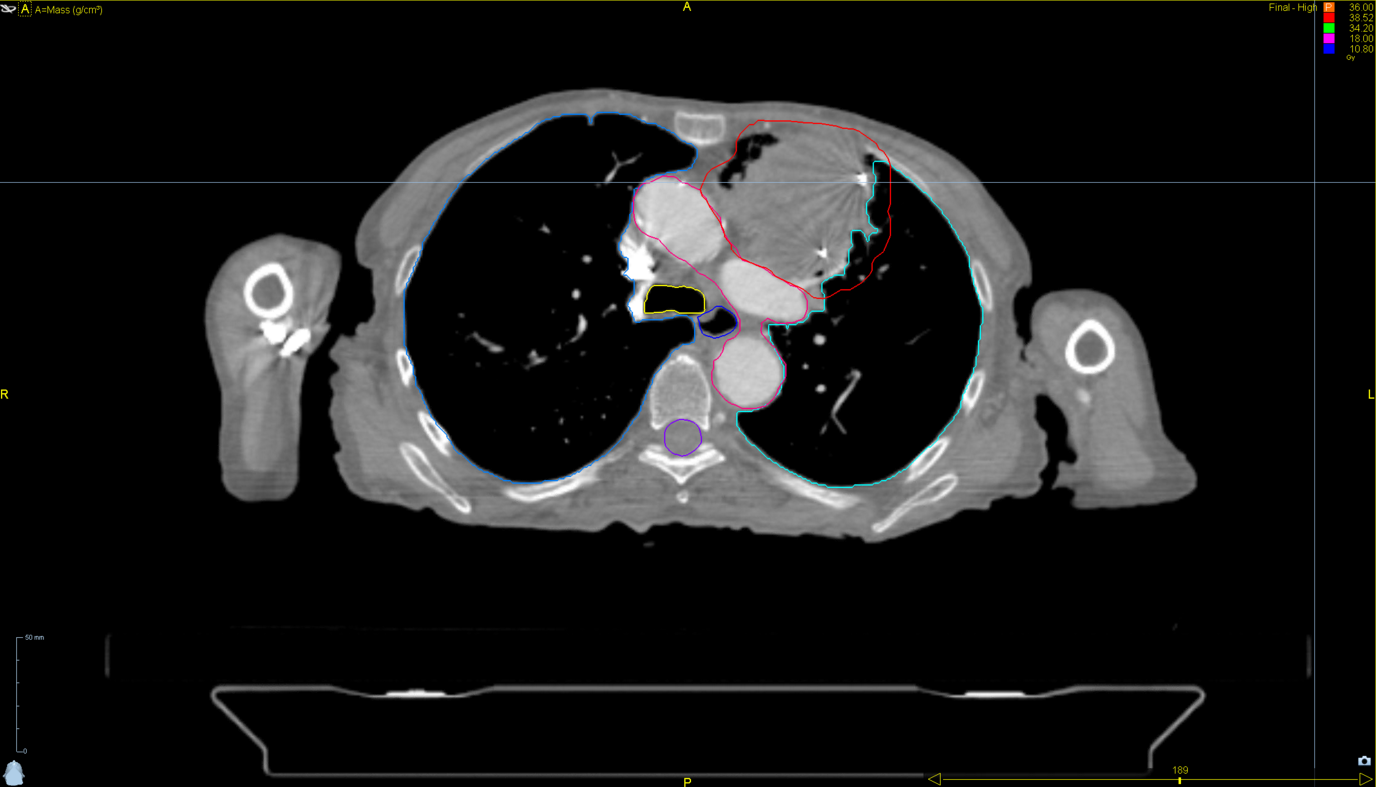

Left Breast with Deep Inspiration Breath Hold

< View All Plan Studies RADIXACT SYSTEM Left Breast with Deep Inspiration Breath Hold Case History AGE: 76-year-oldGENDER: Male Medical History Immidiate tolerance: Grade II dermatitis with eyelid edema, Grade I conjunctivitis resolved with Sterdex Diagnosis: Squamous cell carcinoma of the right lower eyelid Planning CT Images Treatment Plan Images